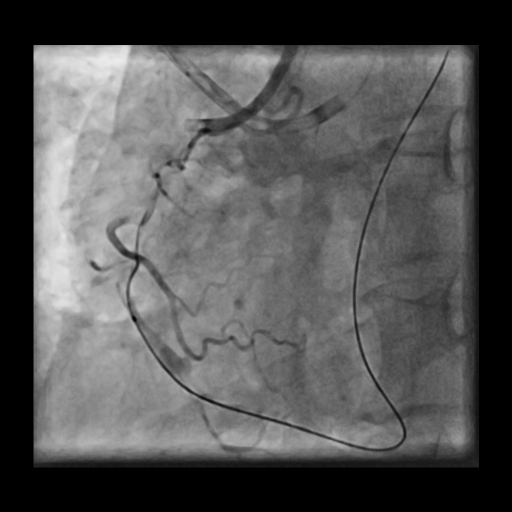

LMCA was engaged with JL 4.0 7 Fr. catheter. First septal collateral was used to reach the distal cap of the lesion using Sion black, Runthrough extrafloppy and Fielder XT-R wire with microcatheter but could not penetrate the distal cap. The lesion could not be crossed with Gaia second and Gladius¢ç Mongo¢ç wire. Antegrade approach was decided to a cross the lesion with Gaia second wire. Antegrade approach caused a dissection resulting in a sub intimal hematoma which extended into the Posterolateral branch. This dissection and the hematoma straightened the vessel near the distal cap. Now this straightening allowed the ASAHI Gladius¢ç Mongo¢ç wire to cross the distal cap retrogradely. The Gladius¢ç Mongo¢ç wire could not be positioned into the true lumen. Now to avoid further dissection proximally the Mongo wire was exchanged with Pilot 150 wire. This wire could cross the proximal cap and finally into the guide catheter. Pilot 150 wire was exchanged with Choice Floppy LS 300 cm which was externalized. A finecross microcatheter was advanced over this wire antegradely. Retrograde microcatheter removed and rest of the case was completed via antegrade approach over Runthrough NS Floppy wire. Lesion was predilated with 2.5x12 mm NC balloon @ 12 atm. Promus Elite 2.75x38 mm DES deployed in mid to distal RCA @ 12 atm. An overlapping stent Xience Xpedition 3.0x28 mm DES deployed from ostium to mid RCA @ 11 atm. Post dilatation with 3.25x10 mm NC balloon @ 11 atm. Distal TIMI III flow achieved.

PTCA 2.mp4